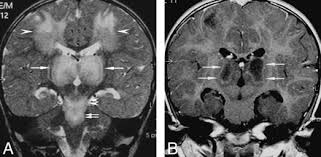

- Magnetic Resonance Imaging (MRI) – The key diagnostic tool. It shows bilateral symmetric lesions in the thalamus, brainstem, and other brain regions.

- The severity of brain lesions seen on MRI